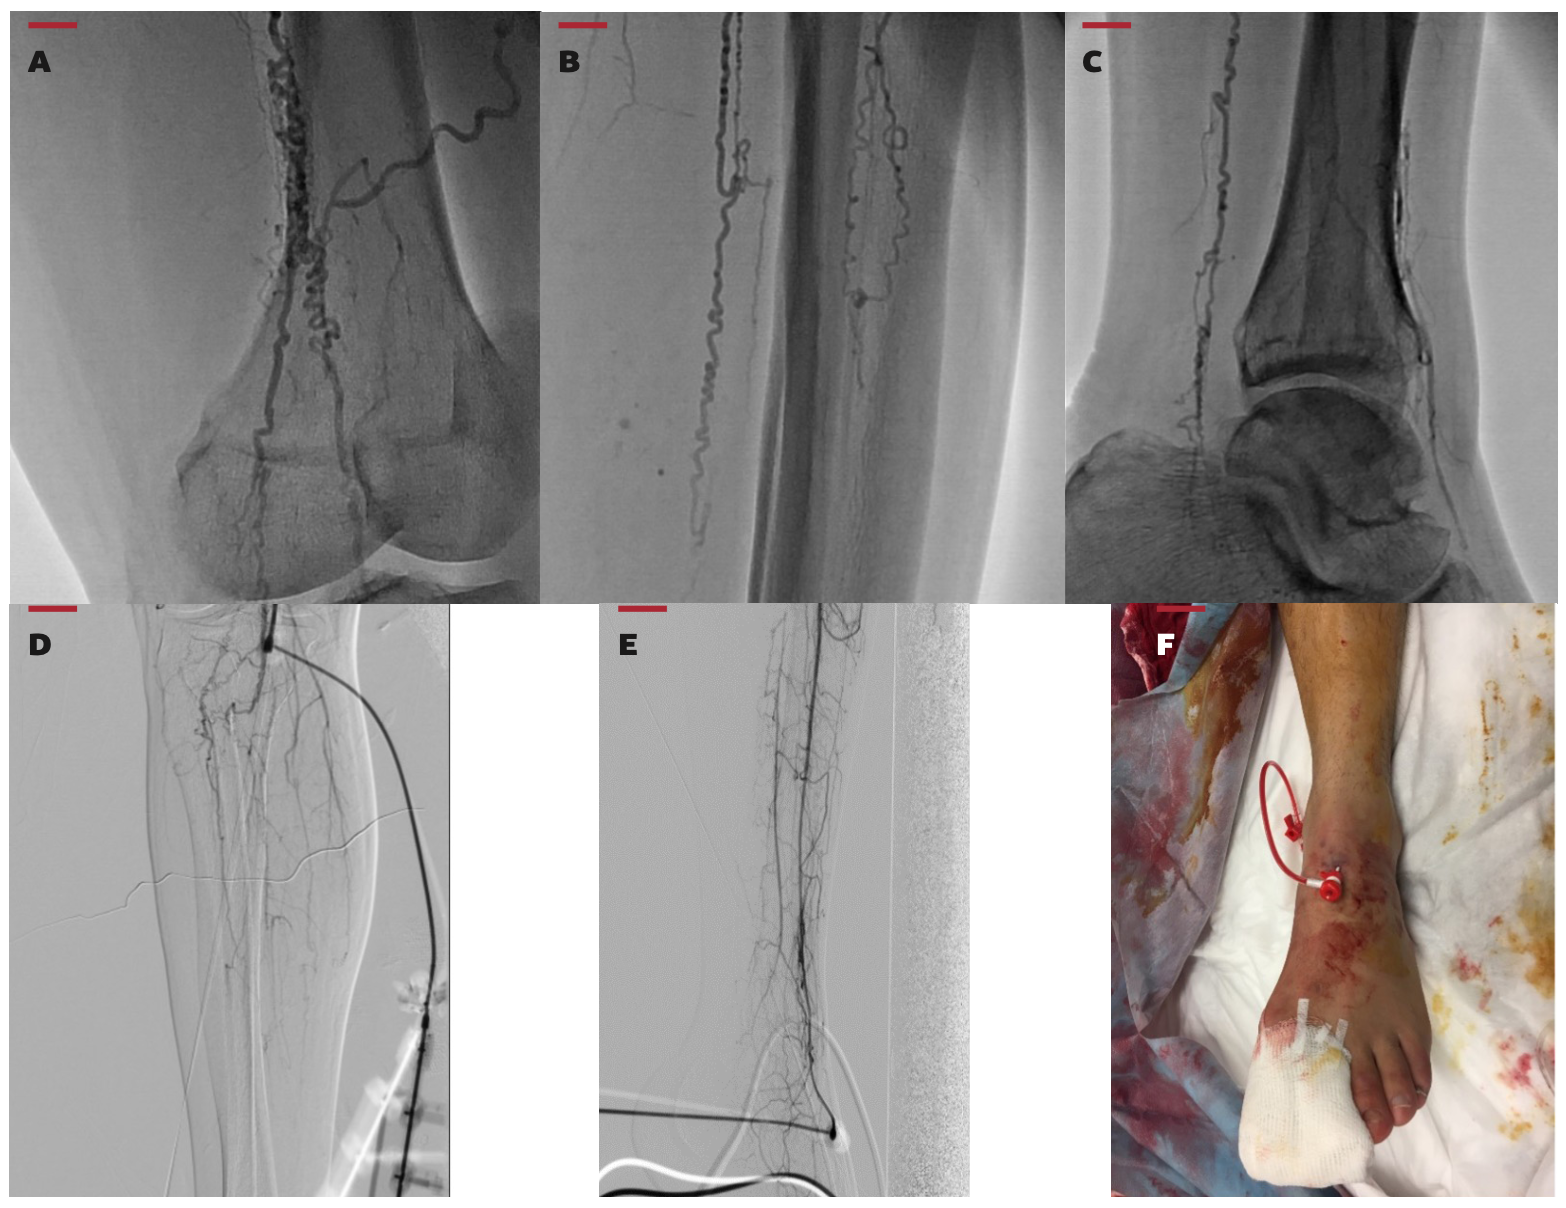

After confirming distal run-off and a proper distal segment consistent with the angiosome concept, transpedal puncture was performed using a micropuncture entry needle with guidance by antegrade contrast injection. Anteroposterior and lateral views were used in puncturing the dorsalis pedis artery and tibialis posterior artery, respectively. However, the peroneal artery—a difficult access site—was punctured in contralateral 30° oblique view while the patient’s hip was abducted and externally rotated with slight knee flexion. Five-Fr x 10-cm-long Radifocus Introducer II sheaths were inserted in cases wherein the distal vascular bed was long enough for cannulation. Heparin 5000 IU and nitroglycerin 100-200 µg were administered into the artery via 5-Fr sheath in order to prevent vasospasm and thrombosis of the pedal arteries. Heparin 100 IU/kg was targeted in all cases and additional heparin was given according to body weight. Periprocedural anticoagulation was adjusted based on activated clotting time (ACT) measurements during the procedures. Figure 1 demonstrates transpedal access via 5-Fr sheath insertion into the dorsalis pedis artery for retrograde percutaneous revascularization of totally occluded popliteal and superficial femoral arteries in a patient with Buerger’s disease.

In patients who had no sufficient landing zone for sheath insertion, specific guidewires such as Fielder FC and/or Fielder XT (Asahi Intecc) were used to advance in the vessel with the support of a dedicated microcatheter (135-cm Corsair Pro; Asahi Intecc). Intraluminal and subintimal crossing techniques such as controlled antegrade and retrograde subintimal tracking (CART), reverse CART, and subintimal tracking and re-entry (STAR) were used for crossing the lesions and wiring the target vessels. The choice between intraluminal and subintimal crossing was left to the operator’s preference. CART, reverse CART, and STAR techniques were performed as previously described.19-21 Dedicated 0.014-inch guidewires manufactured for coronary chronic total occlusion (CTO) revascularizations were used for intraluminal tracking. Hydrophilic and polymer-jacketed guidewires, such as Pilot (0.014-inch Hi-Torque Pilot 50-150-200; Abbott) and Fielder series (0.014-inch Fielder XT/Fielder FC) were used in cases of CART, reverse CART, and STAR techniques. CTO techniques were performed in both the femoropopliteal and tibial target vessels. After the lesions were crossed retrogradely and intraluminal wire positions were confirmed, guidewires were externalized via femoral sheaths and then the procedures were continued to be performed antegradely. Predilation of the lesions was done in accordance with the vessel sizes by using transluminal angioplasty catheters (Armada 14 PTA catheter; Abbott). Afterward, drug-eluting balloon catheters matching with the vessel sizes (Freeway 014 paclitaxel-eluting peripheral dilation catheter; Eurocor Tech) were inflated and held for 3 minutes in the lesions. Drug-coated balloons were used in both the femoropopliteal and tibial vessels. Intra-arterial nitroglycerin (200-400 µg) was given in all cases at the end of the procedures and angiography of the target limb involving the pedal arch was performed. Hemostasis of the retrograde transpedal access site was achieved via internal balloon compression.